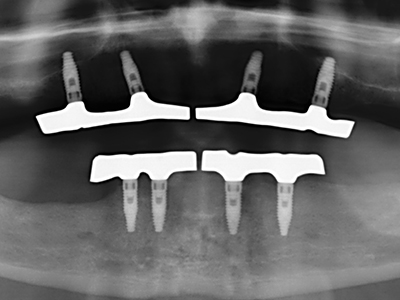

Si es preciso realizar intervenciones quirúrgicas en las que el hueso está en contacto directo con estructuras sensibles, como son los vasos sanguíneos o los nervios, los instrumentos rotativos presentan un enorme potencial de provocar lesiones iatrogénicas. Así, precisamente en la representación de nervios después de una lesión iatrogénica, o en el transcurso de la lateralización de un nervio para resecciones, reconstrucciones o incorporación de implantes, los equipos piezoeléctricos pueden resultar muy útiles para preparar la tapa ósea y retirar las partes de tejido duro cercanas al nervio (fig. 17-20). Por lo general, un ligero contacto del cordón nervioso con el inserto piezoeléctrico no tiene consecuencia alguna; ahora bien, un procedimiento poco cuidadoso con movimientos tipo sierra o piezas de trabajo sobre la base ósea aún existente puede provocar lesiones nerviosas temporales o incluso permanentes. Con todo, el riesgo de sufrir una lesión de este tipo se considera significativamente inferior que en los casos en los que se utilizan sierras y fresas (Pereira, Gealh et al. 2014).

Como ya se ha demostrado en el pasado, básicamente cualquier procedimiento de cirugía de hueso representa una posible indicación para la cirugía piezoeléctrica. Así, la preparación del segmento móvil en la osteogénesis de distracción (fig. 23-25) y en la osteotomía de sándwich puede realizarse con piezas especiales, sin poner en peligro el suministro sanguíneo de la parte crestal, que resulta esencial para el éxito de ambas técnicas (González-García, Diniz-Freitas et al. 2008).

Para la extracción de implantes es posible realizar la preparación de una tapa ósea vestibular que, tras retirar el tornillo del implante, vuelve a fijarse y, de este modo, mantiene el contorno de la apófisis alveolar.